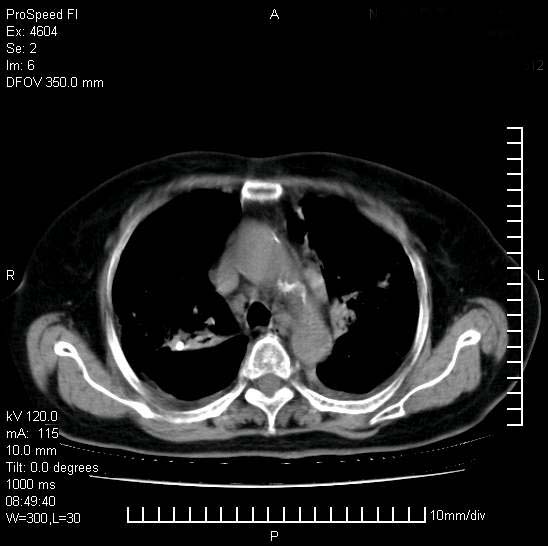

标题: CT15528:女性,79岁,近几日晚上高热,39度,仍咳少量血

十几年前曾患肺结核,一周前突咳血约100ml,中性粒细胞稍高,诊断两上肺陈旧结核,下肺炎症,给予抗炎治疗,近几日晚上高热,39度,仍咳少量血,4天前ct及今天ct上传。

今天ct